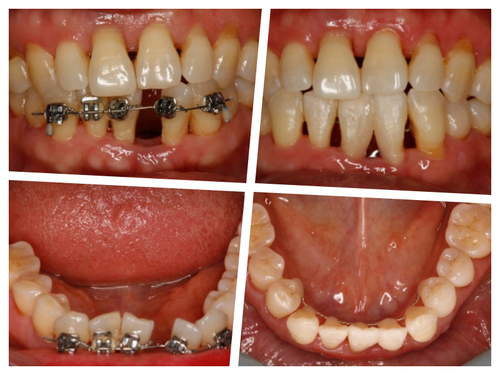

60대 환자분이 이런얘기를 하면 10년 전만해도 불편한 것도 없으신데 굳이 교정을 하셔야할까요? 넌지시 물었었다. 근데 나도 나이가 들면서 이런 생각을 한다. 왜? 나이가 들어서 보기 싫은 건 더 고쳐서 더 자신있게 예쁘게 건강하게 살고 싶은걸.. 니들이 뭘 안다고

그런것 같다. 그래서 네 그게 불만이고 콤플렉스라면 앞니만 간단히 6-7개월 투자하셔서 (당연히 이점이 있다) 대신 그 불편한 기간은 잘 견뎌주셔야 한다고

대부분의 환자분들은 예뻐지는 내 이를 직접보니 잘 견디시는 것 같다.